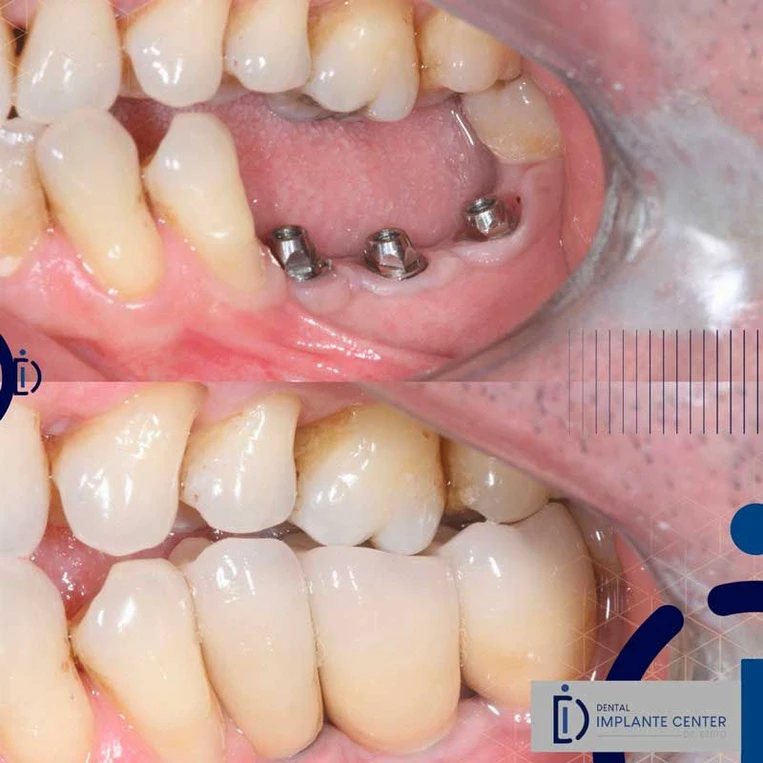

Implante de carga imediata pode ser usado em varias situações:

- Quando paciente não tem dente mais tem osso suficiente para podermos colocar um ou mais dentes provisoriamente.

Implante de carga imediata pode ser usado em varias situações:.

Solução para reabilitação de para quem perdeu todos os dentes da parte superior ou inferior. Composta por uma peça inteira e fixa que reestabelece a qualidade de vida dos pacientes

Técnica moderna que restabelece a função de mastigação e estética em poucos dias. Indicada para pacientes que perderam um dente, dois dentes ou todos os dentes.